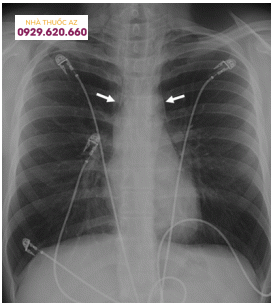

Thật không may, các xét nghiệm trong phòng thí nghiệm có giá trị rất ít trong việc chẩn đoán; tuy nhiên, chúng có thể loại trừ các tình trạng phổ biến hơn trong sự khác biệt bao gồm nhồi máu cơ tim và viêm tụy. Hình ảnh có tầm quan trọng cao trong chẩn đoán Hội chứng Boerhaave. Trong khi chụp X-quang phổi có sẵn, nó là bình thường đối với khoảng 15% trường hợp và không thể được sử dụng để loại trừ chẩn đoán. Các phát hiện X-quang ngực có thể xảy ra bao gồm khí thũng dưới da hoặc trung thất, giãn rộng trung thất, tràn dịch màng phổi, và trong 20% trường hợp, “dấu hiệu V” (vệt không khí chia cắt các mặt phẳng tim sau tim).

Hình 1: Hình ảnh X quang thể hiện tràn khí trung thất do hội chứng Boerhaave